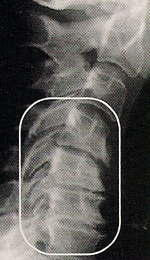

Normal Spinal Neck Curve

The openings between the bones allow nerve roots to exit the spine unimpeeded (without interference). The vertebral edges are smooth and the disc spaces are equal.